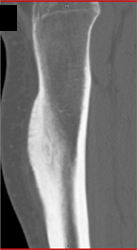

Diagnosis

Pectus With Failed Repair